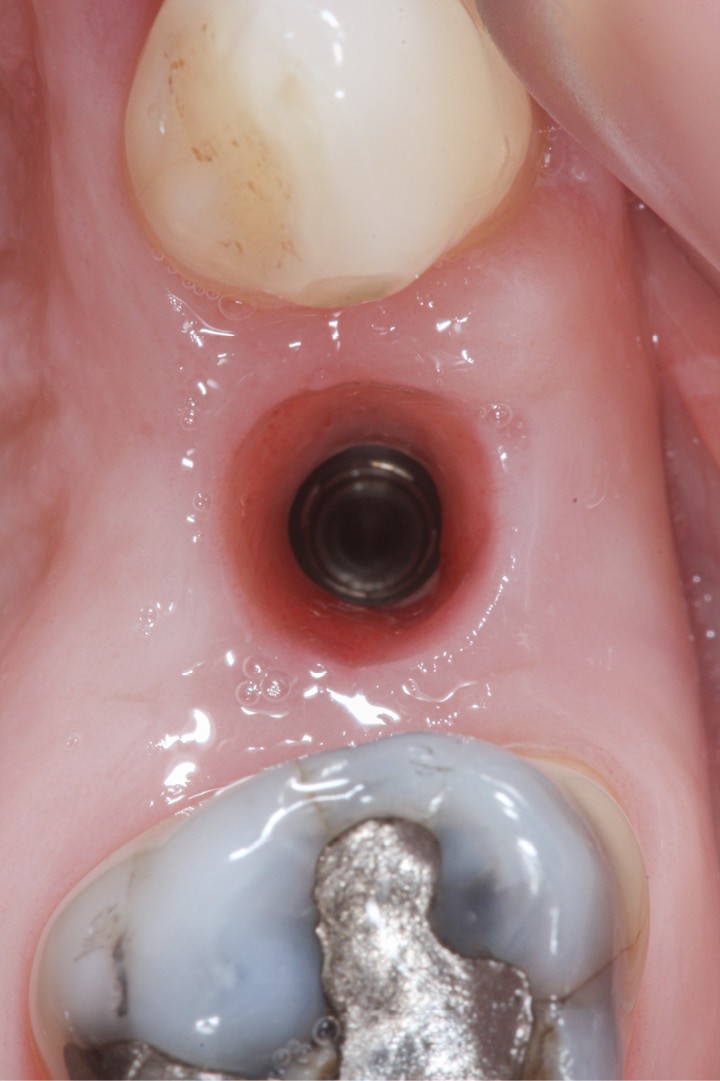

Sur une dent naturelle, le profil d’émergence est la zone de transition entre la racine et la couronne dentaire. En prothèse implantaire, le profil d’émergence se définit comme le contour des éléments prothétiques personnalisés et adaptés à l’architecture gingivale péri-implantaire (fig. 3). Le problème est que les racines dentaires, à la différence des implants qui les remplacent, ne sont pas de section ronde [5]. Les différentes vis de cicatrisation ne permettent pas d’obtenir un profil d’émergence proche de la réalité.

La conception de la partie transgingivale des prothèses répond maintenant à un consensus (profil concave dans la zone profonde dite subcritique, profil convexe au niveau du sulcus marginal, aussi appelé zone critique). Une augmentation du volume prothétique de la zone critique entraînera une récession des tissus péri-implantaires, une diminution de volume de la zone subcritique entraînera…